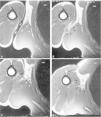

Se sospecha ruptura del LD o de TM, por lo que se solicita resonancia magnética (fig. 3). Se observa una alteración de la señal en la inserción proximal del tendón del LD, con rotura fibrilar completa y retracción del cuerpo del músculo, edema y hematoma localizado en la región axilar.

Figura 3 Imágenes de resonancia magnética seriadas axiales en T1, en la región axilar. Se observa el marcador cutáneo (m) con flechas (c) que indican desestructuración en la zona de la lesión. Retracción muscular del Latissimus dorsi (estrellas blancas).